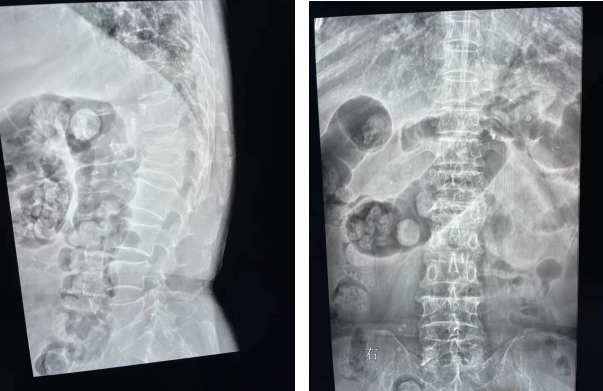

据了解,6月30日上午患者董女士由其家人平车推入医院骨科门诊就诊,骨科吴郑南医师接诊后详细询问病史,仔细查体,并进行X射线等检查后,确诊为胸12椎体老年性骨质疏松伴病理性骨折,收住入院。既往高血压病史、海默尔综合征,患者时而清醒时而糊涂,老年痴呆症严重。